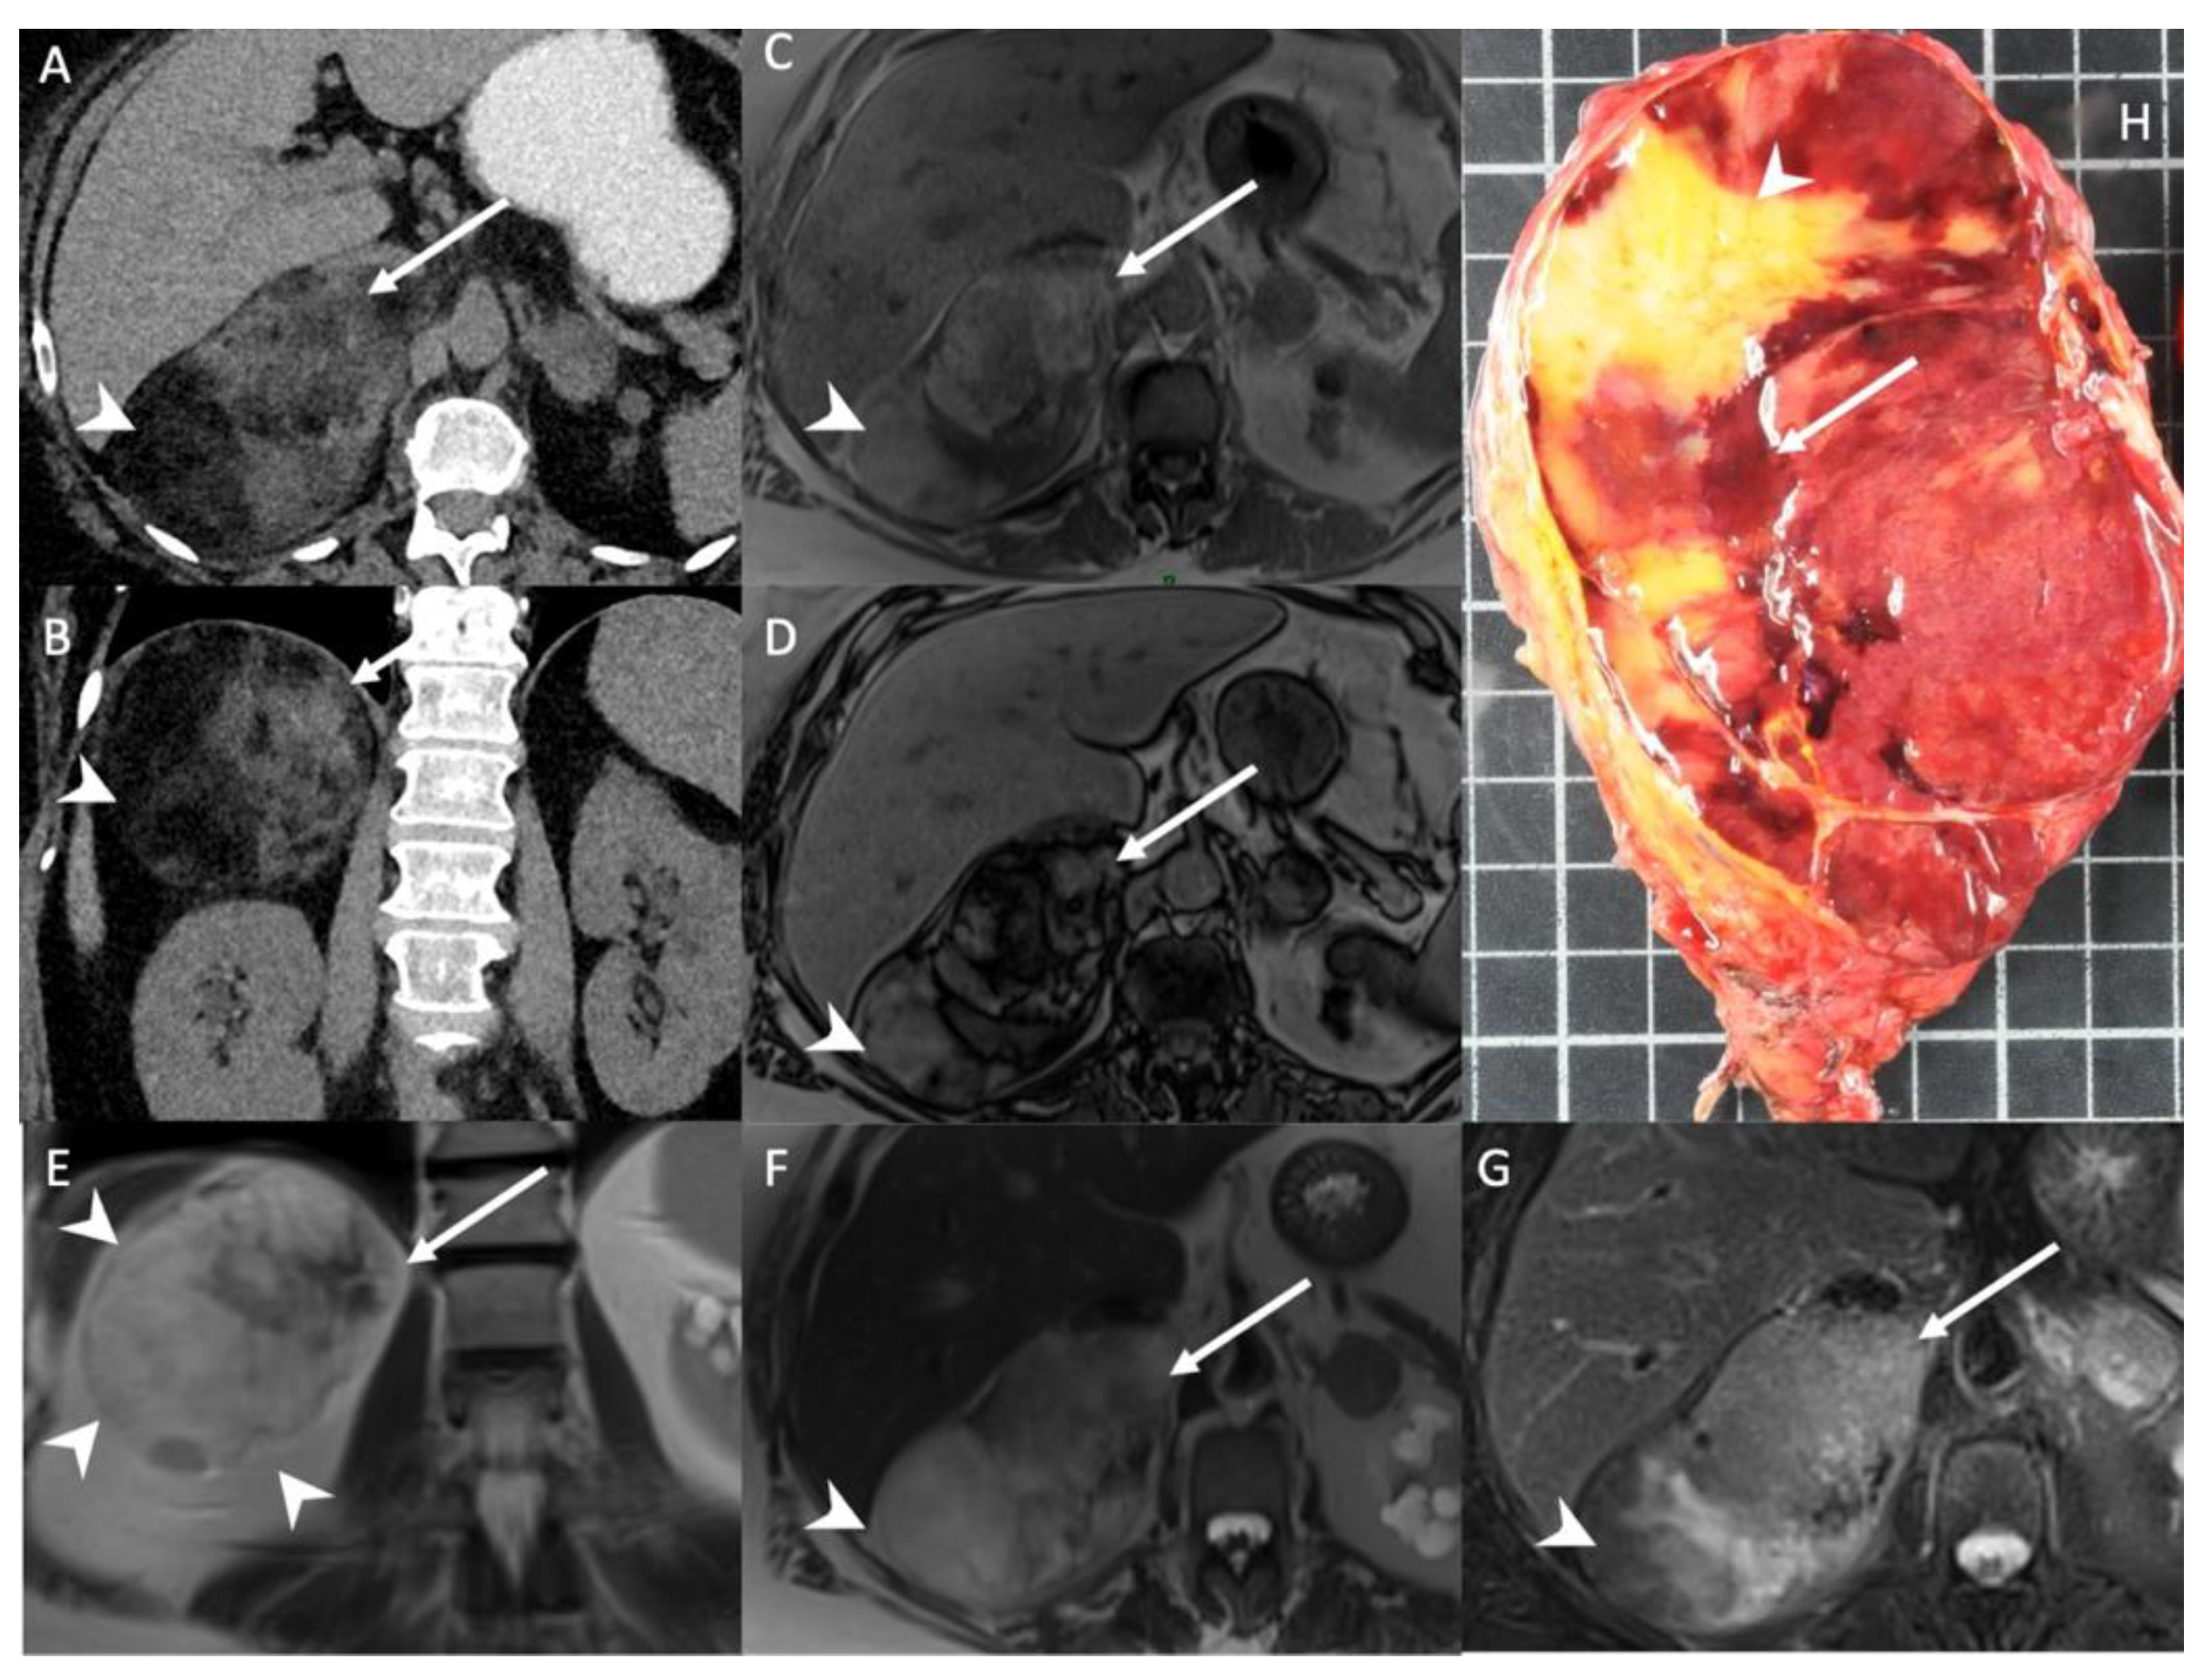

- Jacques, A.E.; Sahdev, A.; Sandrasagara, M.; Goldstein, R.; Berney, D.; Rockall, A.G.; Chew, S.; Reznek, R.H. Adrenal phaeochromocytoma: Correlation of MRI appearances with histology and function. Eur. Radiol. 2008, 18, 2885–2892. [Google Scholar] [CrossRef]

- Tufton, N.; White, G.; Drake, W.M.; Sahdev, A.; Akker, S.A. Diffusion-weighted imaging (DWI) highlights SDHB-related tumours: A pilot study. Clin. Endocrinol. (Oxf.) 2019, 91, 104–109. [Google Scholar] [CrossRef]

- Kostiainen, I.; Hakaste, L.; Kejo, P.; Parviainen, H.; Laine, T.; Loyttyniemi, E.; Pennanen, M.; Arola, J.; Haglund, C.; Heiskanen, I.; et al. Adrenocortical carcinoma: Presentation and outcome of a contemporary patient series. Endocrine 2019, 65, 166–174. [Google Scholar] [CrossRef] [PubMed]

- Kedra, A.; Dohan, A.; Gaujoux, S.; Sibony, M.; Jouinot, A.; Assie, G.; Groussin Rouiller, L.; Libe, R.; Bertherat, J.; Soyer, P.; et al. Preoperative Detection of Liver Involvement by Right-Sided Adrenocortical Carcinoma Using CT and MRI. Cancers (Basel) 2021, 13, 1603. [Google Scholar] [CrossRef] [PubMed]